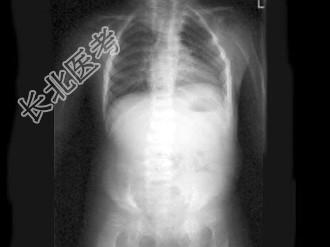

- 单项选择题女,3岁, 身高不增,智力正常, 结合图像,最可能的诊断是 ( )

C、黏多糖贮积症Ⅳ型